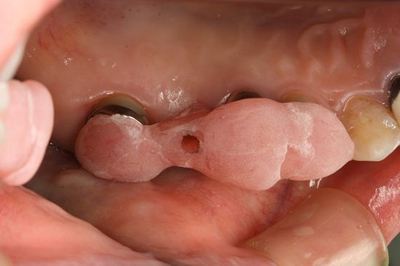

ドリルガイドの適合を確認します。

ドリルガイドに沿って安全な部分までドリリングして深度ゲージを挿入します。